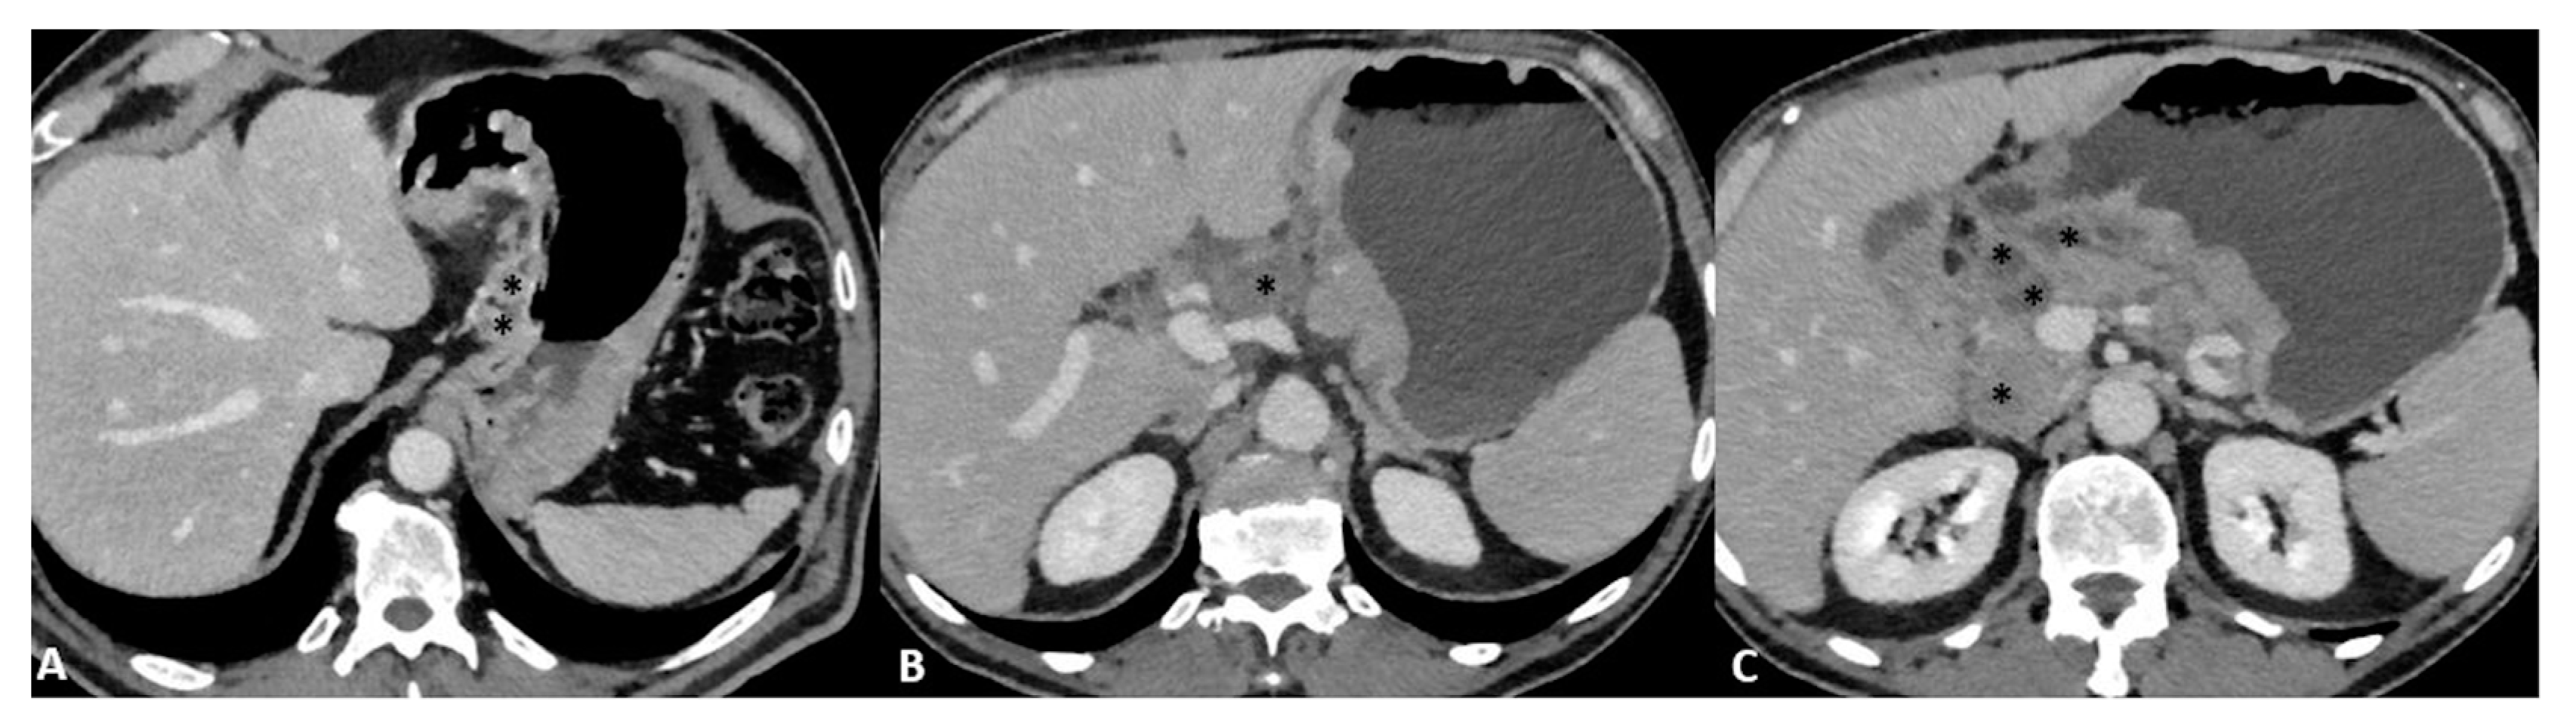

Finally, T4a also demonstrates serosal involvement, which makes the differential with T3 very difficult. This is especially true because the gastric serosa is not well defined due to the different amounts of subserosal adipose tissue. To solve the differential, T4a frequently shows solid nodules or band-like stranding in the perivisceral adipose tissue (Figure 4).

Figure 4.

(A) Axial 2D image in the portal venous phase of a T4a gastric cancer in a 66-year-old female patient. The tumor (thick arrow) is the enhanced wall thickening in the lesser curvature side of the middle body of the stomach which penetrates the serosa with some solid deposits (white asterisk) in the perivisceral fat tissue and some pathologic lymph nodes (thin arrow) with necrotic-colliquative components inside. (B) Axial 2D image of a T4a gastric cancer in a 78-year-old female patient. The tumor (thick arrow) is the enhanced wall thickening on the lesser curvature side of the low body of the stomach which penetrates the serosa with some spiculatures in the perivisceral fat tissue and a pathologic lymph node (black asterisk).

T4b shows extension into an adjacent structure and shows the loss of the fat plane between the gastric mass and adjacent organs (Figure 5).

Figure 5.

T4b gastric cancer in a 74-year-old female patient. (A,B). Axial 2D images in the portal venous phase and (C) Coronal multiplanar reconstruction showing (thick arrows) a bulky tumor of the middle-low body of the stomach and of the gastric antrum with necrotic-colliquative components inside, ulcerative alterations and some solid deposits (black asterisks) in the perivisceral fat tissue. The tumor fistulizes and infiltrates the transverse colon (thin arrows).